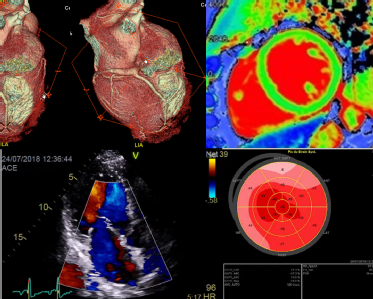

Multimodality Imaging Toolkit on Aortic Stenosis

The novelty of this project is the advantage of assessing a pathology using four imaging techniques (Echo, Cardiac Magnetic Resonance, Nuclear Cardiology & Cardiac Computed Tomography).